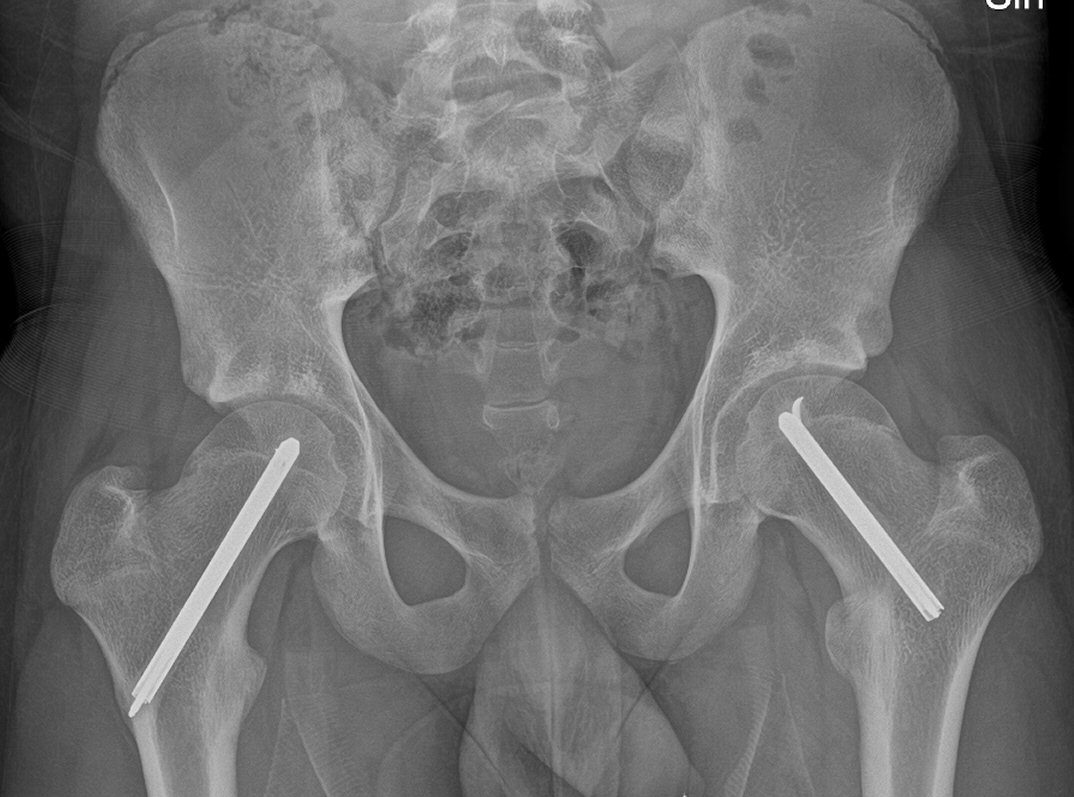

Fysiolys vänster höft akut, efter primär operation resp. innan spikextraktion efter 6 år

- T.ex. LIH-spikning med 1 eller 2 spik, incision betydligt mer anteriort än vanligt, spikarna riktas mer posteriort [3]

- Ofta profylaktisk spikning kontralateral sida pga. upp till 80 % risk för bilateral fyseolys [3]